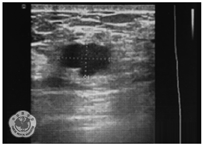

入院时查体:体温36.5 ℃,脉搏74次/min,呼吸18次/min,血压134/76 mmHg(1 mmHg=0.133 kPa);全身浅表淋巴结未触及明显肿大,心肺无异常,左侧乳腺9点钟可触及一肿块,大小约2.0 cm×2.0 cm,质地韧,边界欠清楚,活动度欠佳,与皮肤轻度粘连;右侧乳腺未触及肿块,双侧腋窝未触及肿大淋巴结。辅助检查:甘油三酯1.84 mmol/L(参考值:0.7~1.7 mmol/L),血清总胆固醇、高密度胆固醇、低密度胆固醇均在正常范围。乳腺彩色超声:左乳9点钟方向可见一大小约1.0 cm×0.6 cm×1.2 cm混合性回声团,形态欠规则,边界欠清晰,后方回声无衰减,周边未见血流信号,双侧腋窝未见明显异常回声,提示为左乳囊实性病灶,BI-RADS 4A类(图1)。腹部彩色超声显示患者有脂肪肝及子宫肌瘤。胸部CT显示右肺上叶、双肺下叶胸膜下结节灶,右肺上叶及左肺下叶钙化灶。入院诊断为左侧乳腺恶性肿瘤,建议行乳腺空心针穿刺活组织检查,但患者拒绝。

注:左乳9点钟方向可见一1.6 cm×1.0 cm×1.2 cm混合性回声团,形态欠规则,边界欠清晰